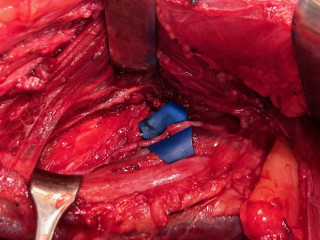

Unusual nerve compression from a surgical and therapeutic point of view

Patricia Kammermann, Bern; Lena Fuest, Bern

Patricia Kammermann1, Lena Fuest1 (1Berner Handzentrum, Bern)

Contexte

La fracture de l’hamulus ossis hamati est une lésion rare et souvent négligée. En raison de sa proximité anatomique avec le rameau profond du nerf ulnaire, une fracture peut provoquer une irritation ou une compression dans la loge de Guyon. Cela peut causer un déficit moteur, en particulier une faiblesse de la musculature intrinsèque, entraîner une perturbation de la motricité fine ainsi qu’une possible déformation en griffe des quatrième et cinquième doigts.

Objectif

L’objectif de cette étude de cas est de faire prendre conscience d’un lien potentiel entre une fracture de l’hamulus et une neuropathie ulnaire. Il s'agit notamment de souligner qu’en cas de déficit moteur isolé du nerf ulnaire sans déficit sensitif, il convient de rechercher spécifiquement une origine osseuse.

Méthodologie

En août 2024, un patient âgé de 21 ans a fait une chute à vélo sur sa main gauche. L’évaluation post-traumatique montrait une perte d’extension indolore de l’articulation PIP des doigts 4 et 5. Une radiographie conventionnelle a d'abord permis d'exclure une fracture, puis une échographie a permis d'écarter une lésion tendineuse. Près de trois mois plus tard, une atrophie au niveau du premier interosseux dorsal était visible cliniquement. Plus tard, une tomodensitométrie a révélé une fracture à la base de l'hamulus ossis hamati.

Sur le plan thérapeutique, le patient a tenté de renforcer sa musculature intrinsèque à l’aide de l’électrothérapie ainsi que de maintenir la mobilité passive de ses articulations digitales. Des stratégies pour gérer le quotidien lui ont également été enseignées.

Quelques semaines après la neurolyse et l’ostéosynthèse de l’hamulus ossis hamatum, la fonction du nerf ulnaire s’est totalement rétablie.

Résultats

Un déficit moteur du nerf ulnaire peut être dû à une fracture non diagnostiquée de l’hamulus ossis hamati. De petites nuances dans l’anamnèse et l’examen clinique font ici toute la différence et peuvent contribuer, grâce à la collaboration entre le chirurgien et le thérapeute de la main, à établir rapidement un diagnostic afin de lutter de manière ciblée contre l'atrophie musculaire. Une collaboration étroite et une communication directe entre la chirurgie et la thérapie de la main sont indispensables.